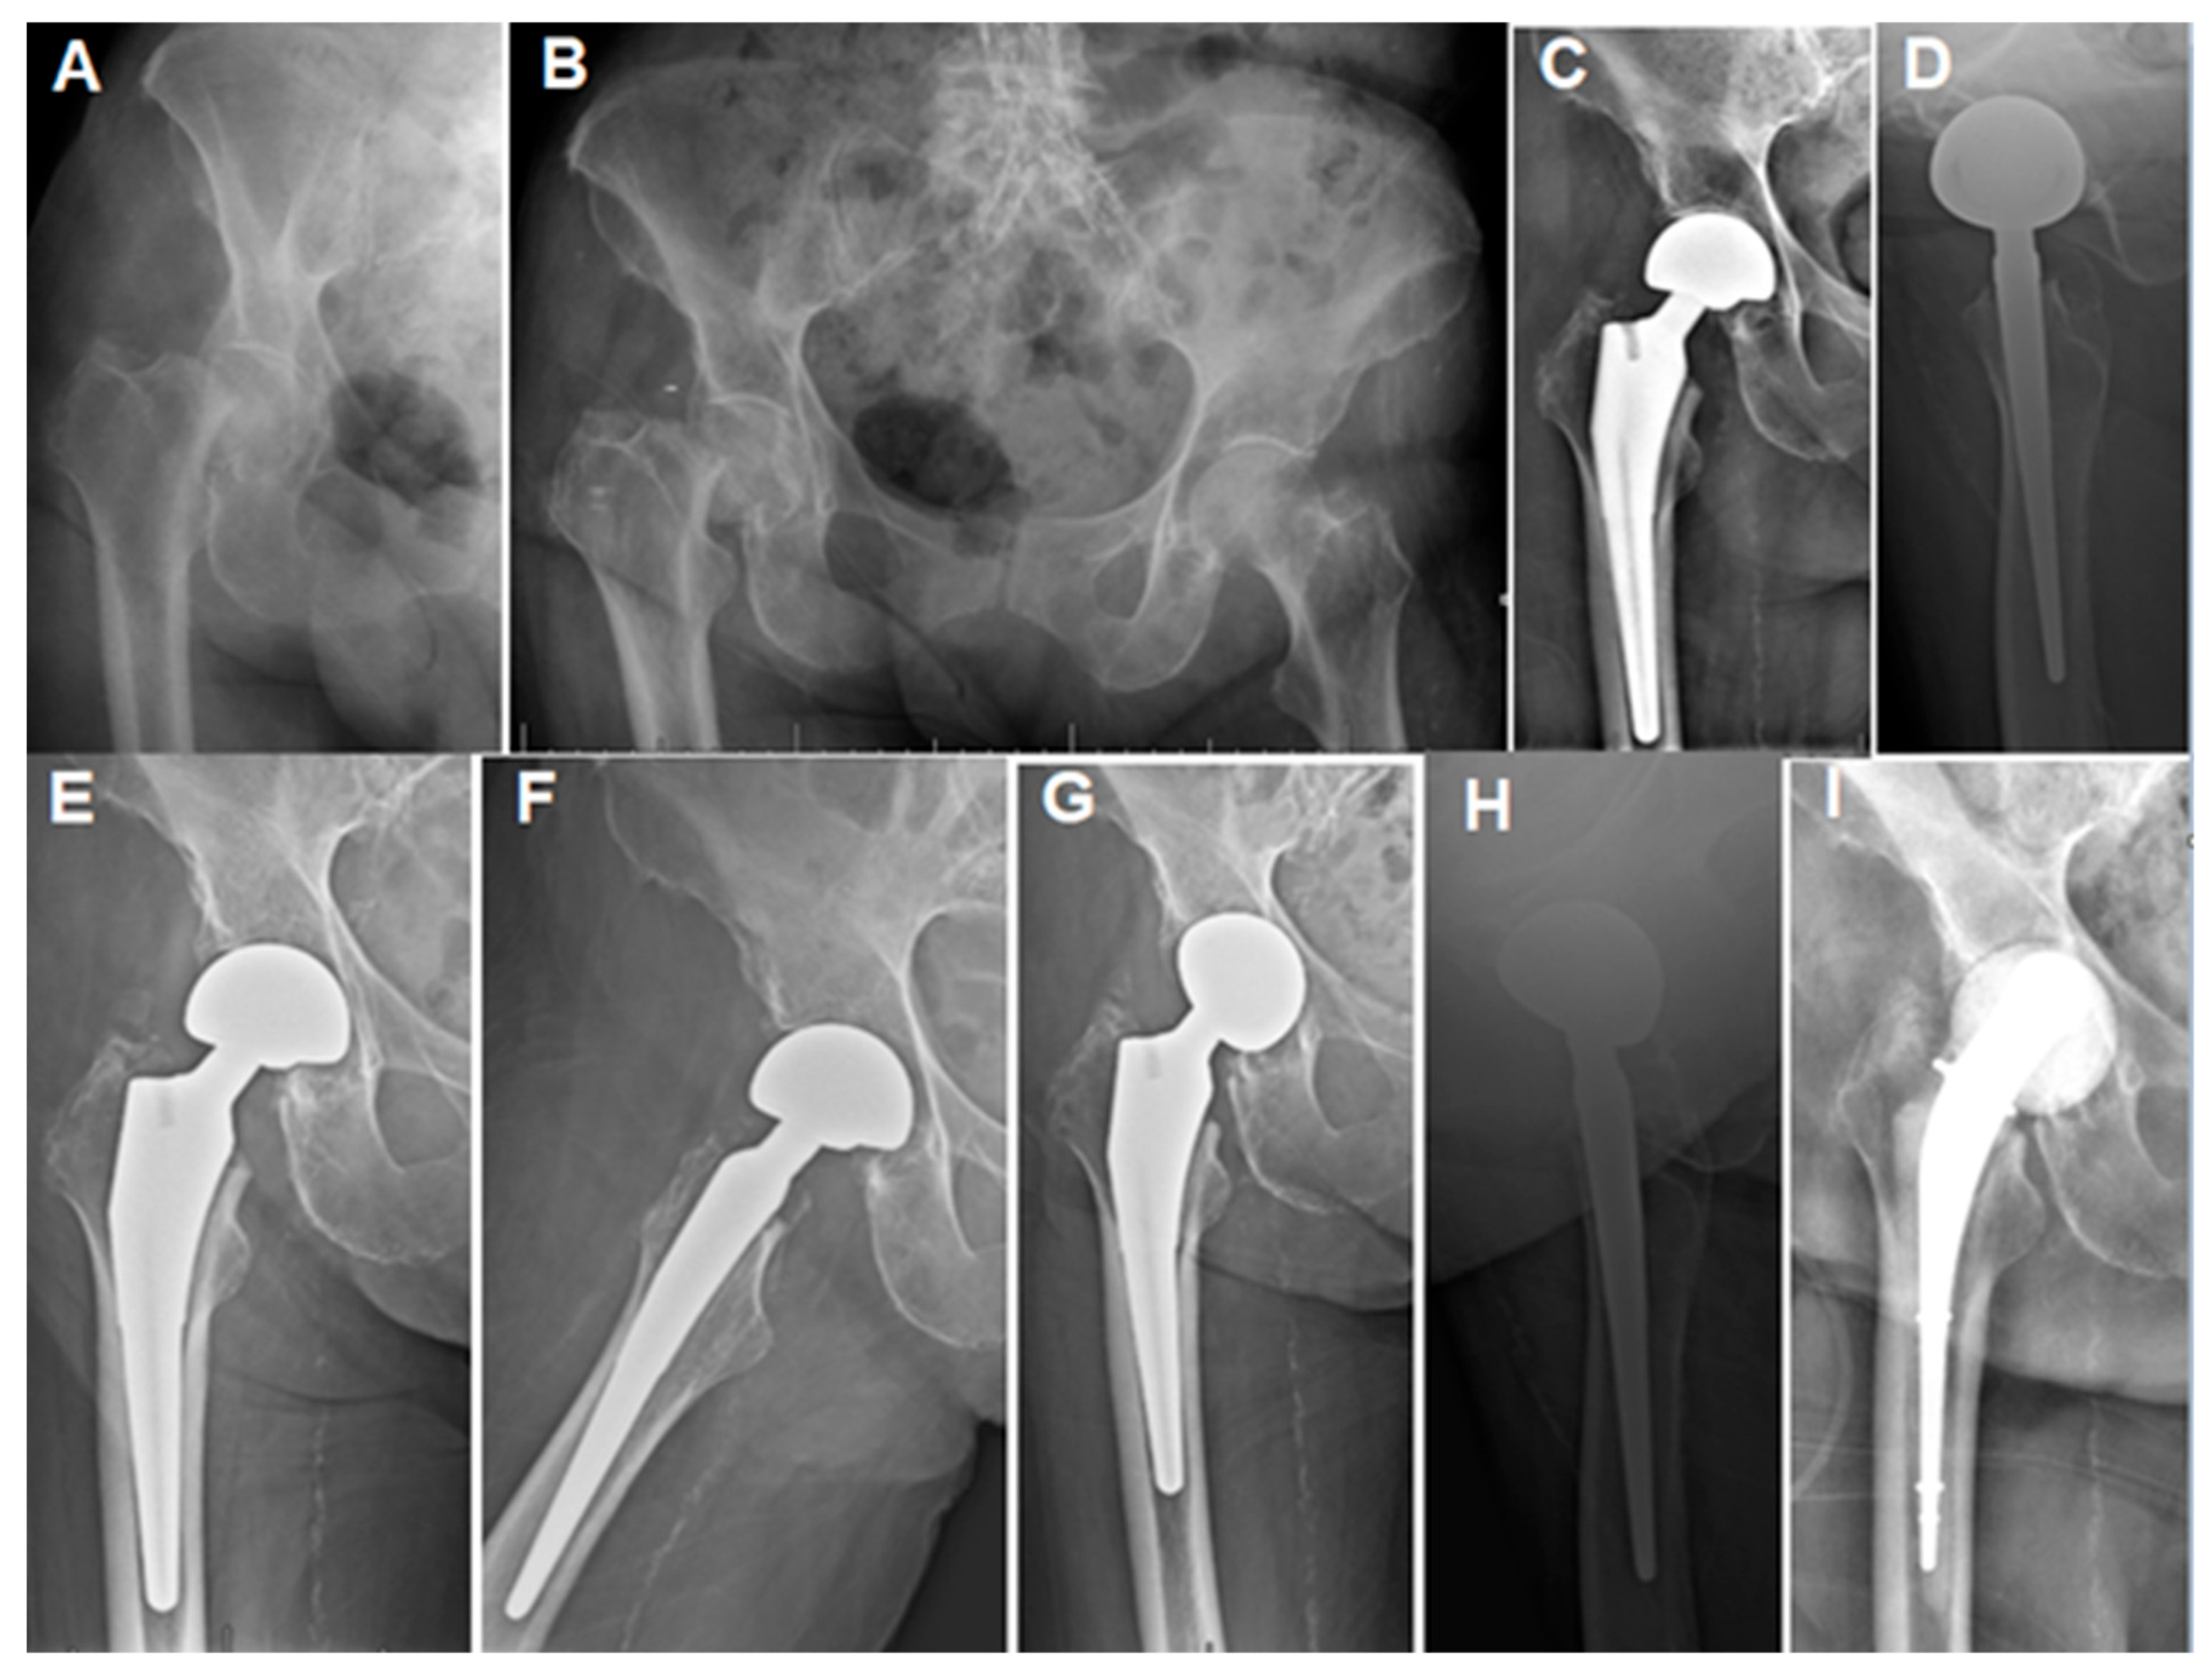

Figure 3.

Case 4 (Table 1): (A,B) Plain hip radiographs of a 93.2-year-old female showing displaced right femoral neck fractures. (C,D) Immediate postoperative hip radiographs showing cementless bipolar HA with stable components. (E,F) Three-month plain radiographs showing stable components and mild radiological erosion. (G,H) Fourteen-month postoperative radiograph showing acetabular erosion. The patient presented at this stage with a 2-week history of hip pain and a discharging wound sinus. (I) AP radiograph after debridement, implant removal, and spacer insertion. The patient received a 6-week IV antibiotic regimen and was followed for a total of 9 months after spacer insertion (including the antibiotic period) before being lost to follow-up.